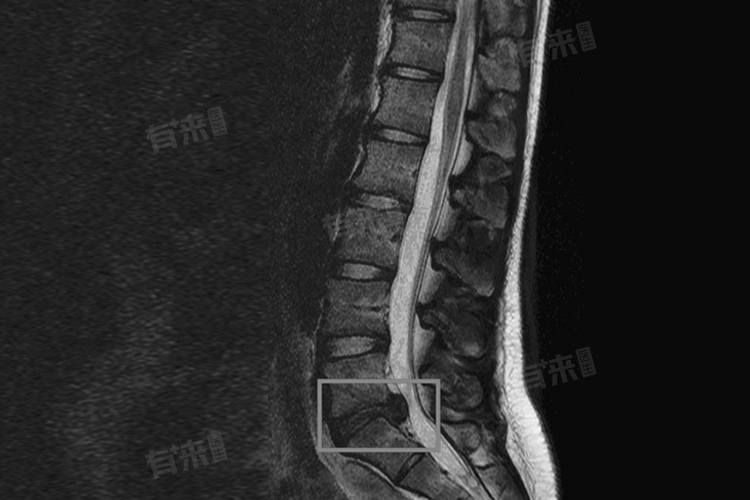

椎间盘真空征的诊断主要依赖于影像学检查,如X光片、CT扫描或MRI等,能够清晰地显示椎间盘内部的空隙和气体充填情况,从而明确诊断。医生会根据患者的症状和影像学检查结果,综合评估病情,制定合适的治疗方案。